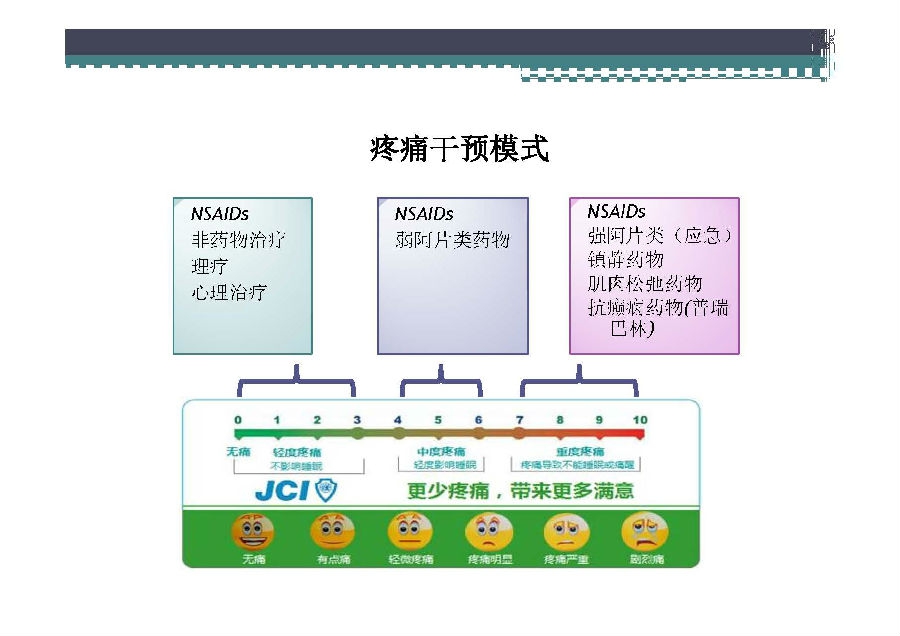

对于关节外科而言快速康复实际上是以病人加速舒适康复为目的,加强围术期的综合管理,包括疼痛和睡眠管理、血栓预防管理、感染预防管理、围术期血液管理,减少放置引流管、尿管、减少止血带应用,减少术后恶心呕吐,尽早进食,尽早康复等,逐步达到无血、无痛、无栓、无感、无肿、无管、无吐、无带等优良效果。为此,小编特邀王坤正教授等多位关节外科的专家参与撰写快速康复外科在关节外科的应用的主题文章,共话“人工关节置换快速康复”新理念,探讨建立符合我国特色的关节置换围手术期管理与快速康复体系,促进我国关节外科技术整体发展与提高。